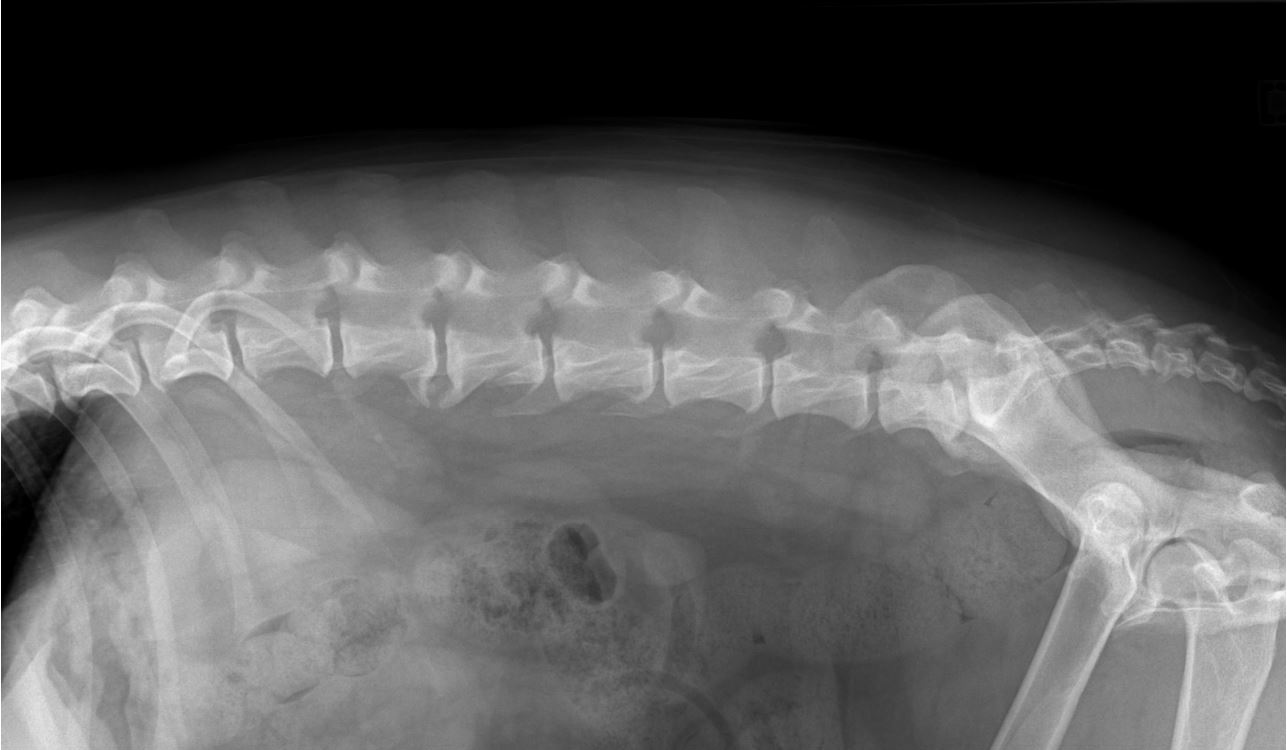

La radiographie de profil de la colonne lombaire montre des ostéophytoses entre L2-L3 et L7- Sacrum. Les radiographies de face et profil des carpes montrent des congruences articulaires normales et l'absence d'ostéophytose.

Photographie issue de la collection privée de l’auteur – Radiographie colonne lombaire profil droit Carmella